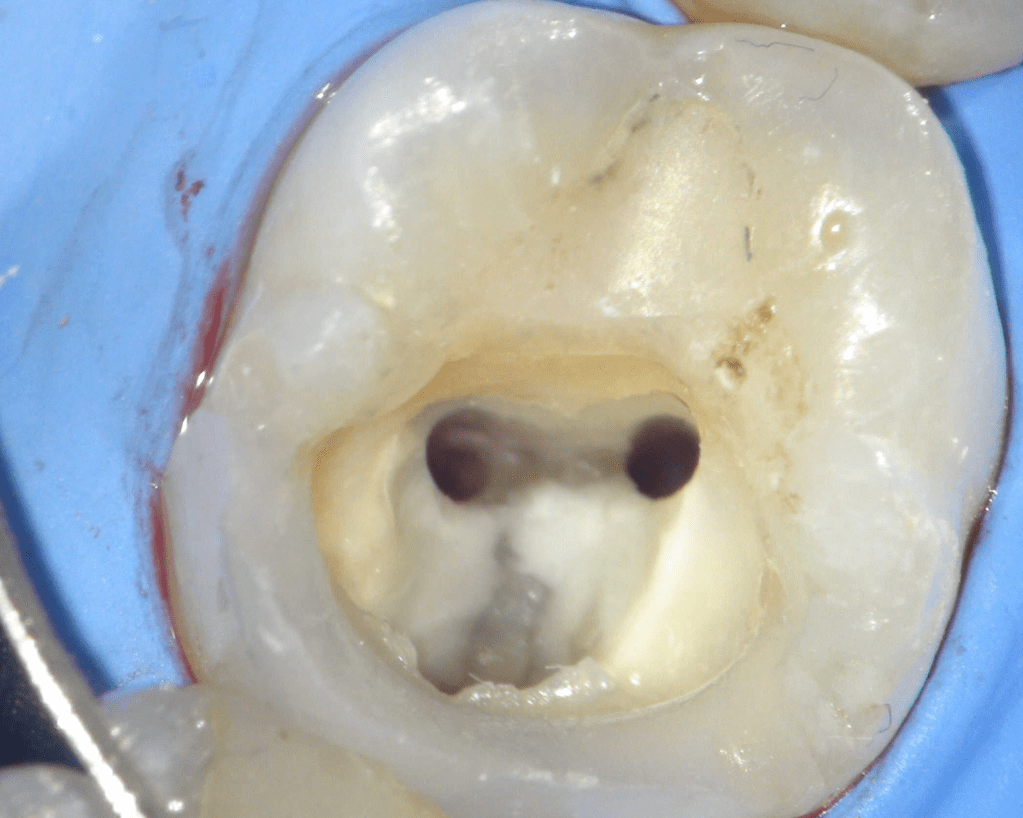

Reco preendo + 4 conductos molar superior